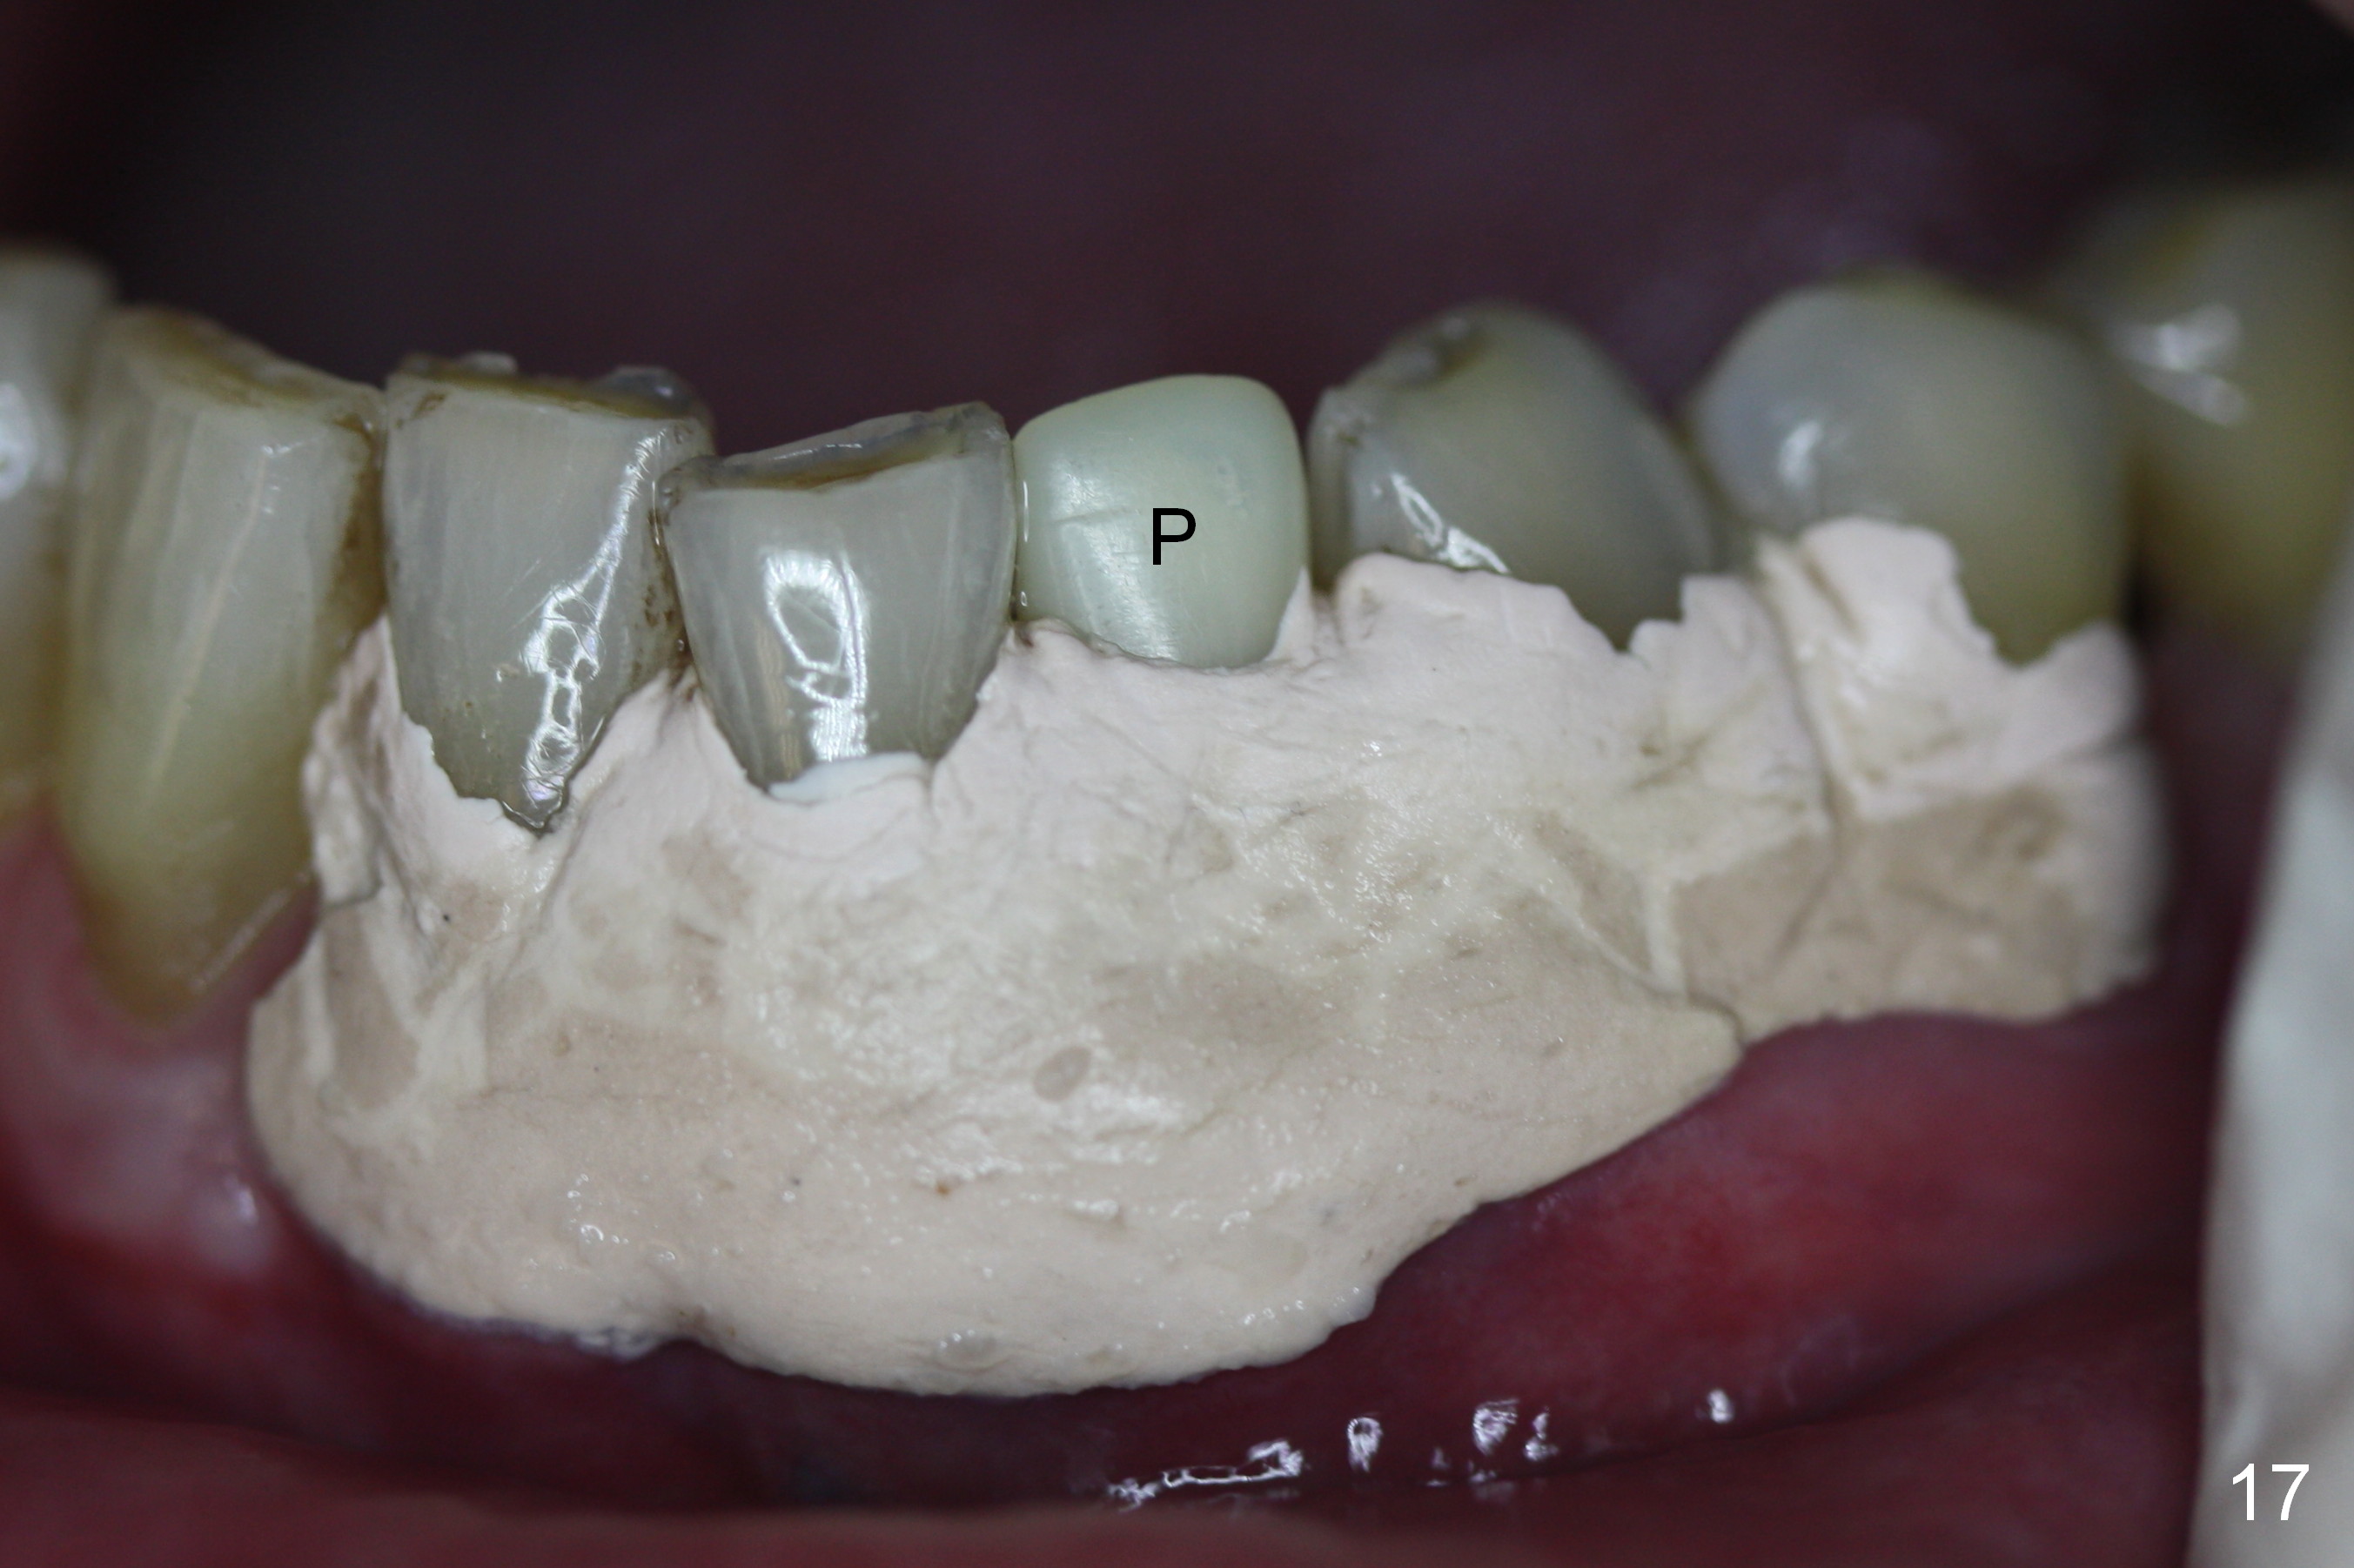

A 74-year-old man has several missing teeth (Fig.1). His 1st goal is to replace the lower left lateral incisor (Fig.2). The residual root has an apical lesion (Fig.3 *). To describe intraop findings, a CT image of a different patient is used (Fig.4 coronal section; B: buccal; L: lingual). After extraction, the buccal plate is found to be thin and low (Fig.5 arrowheads). A 1.5 mm pilot drill (Fig.6 red line) is used to initiate osteotomy in the lingual plate of the socket. Once the drill penetrates the lingual plate, the trajectory changes and the depth is 17 mm from the gingival margin (Fig.7). A PA is taken (Fig.8); it appears that the osteotomy can be extended more apically. When the pilot drill extends to 20 mm, there is sudden empty feeling. The lingual plate has perforated (Fig.9). A new osteotomy is established buccally (Fig.10 pink). To avoid buccal plate perforation, especially in the buccal undercut area (>), the coronal end of the drill has to be tilted buccally (<--). An angled abutment (3x20 mm, 15°) is placed (Fig.11,12). The abutment is modified (Fig.13,14) to accommodate an immediate provisional (Fig.15,16 P). Perio dressing is to be applied to prevent the bone graft from getting dislodged buccally (Fig.15). The dressing is in place 7 days postop (Fig.17).

Five months postop, the peri-implant space reduces (Fig.18). A keratinized band forms buccal to the implant (Fig.19 *). The provisional dislodges probably due to the buccal placement (Fig.20).